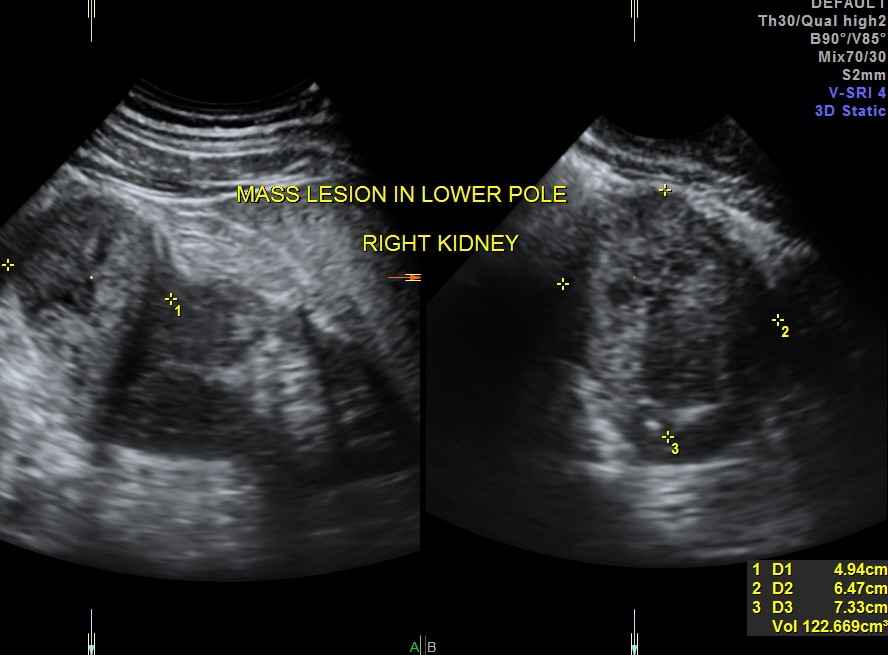

The right kidney pictures are given below. Mass lesion seen in the lower pole .

3 D images are given below.